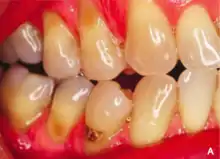

يظهر السحج في كثير من الأحيان عند الملتقى المينائي العاجي ويمكن أن يحدث بسبب العديد من العوامل المساهمة، وكل ذلك له القدرة على التأثير على سطح السن بدرجات متفاوتة. [4]

قد يختلف المظهر تبعًا لسبب التآكل، ومع ذلك فإنه يوجد بشكل شائع بـشكل حرف V ويكون بسبب الضغط الجانبي المفرط أثناء تنظيف الأسنان. السطح يكون لامع وغير مصاب بالتسوس، وأحيانًا يكون الحيد عميق بما يكفي لرؤية حجرة اللب داخل السن نفسها.

مع حدوث فقدان عنقي غير نخري بسبب السحج، قد يؤدي ذلك إلى عواقب وأعراض مثل زيادة حساسية الأسنان تجاه المواد الساخنة والباردة وزيادة تراكم اللويحة مما يؤدي إلى تسوس الأسنان وأمراض اللثة، وصعوبة استخدام تركيبات سنية مثل المثبت وطقم الأسنان وصعوبة تثبيتها في الأسنان، وأيضًا يكون غير مرضي من الناحية الجمالية لبعض الناس. [3]